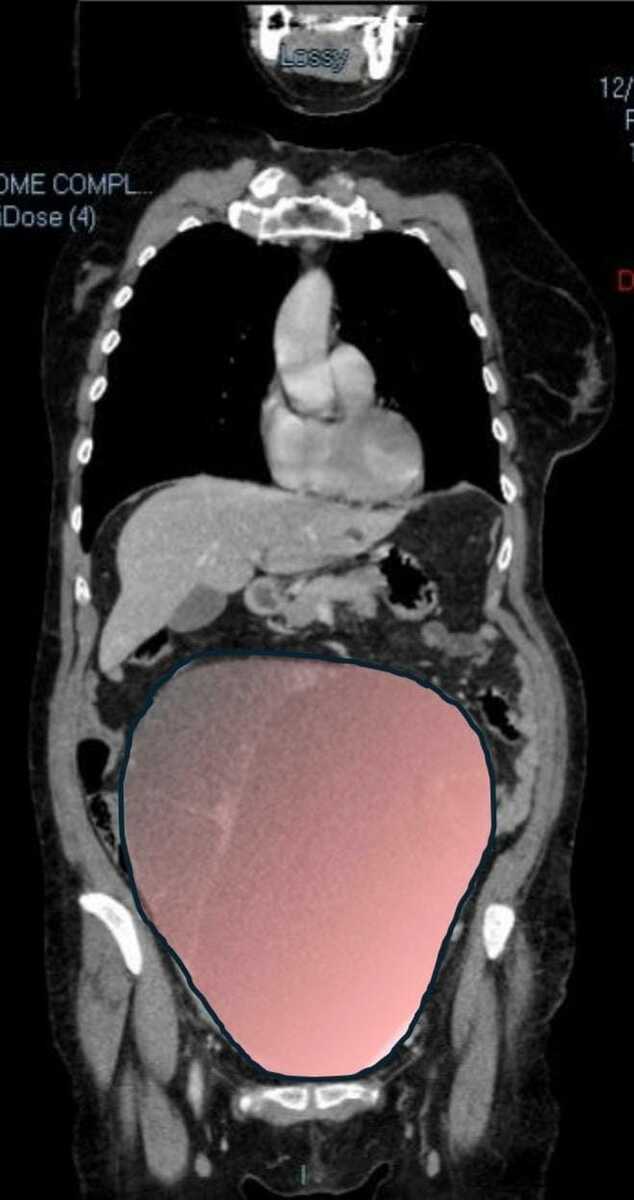

Per mesi la gigantesca cisti ovarica, con un diametro di circa 28 centimetri, è rimasta nascosta, senza dare segnali evidenti. La paziente non si era accorta di nulla. L’allarme è scattato quando la massa, associata alla presenza di una seconda neoplasia intestinale, ha iniziato a comprimere il colon, provocando sintomi acuti ed improvvisi fino a una grave difficoltà intestinale non più ignorabile.

Fondamentale in questa fase il contributo della Radiologia dell'ospedale Sant’Anna, che fornisce l’imaging preoperatorio indispensabile per affrontare un quadro clinico di eccezionale complessità.

Durante l’intervento emerge tutta la gravità della situazione. La gigantesca neoplasia ovarica viene asportata: pesa circa 6 chilogrammi, con un volume paragonabile a quello di una gravidanza gemellare a termine. Ma non è l’unica minaccia. I sintomi più pericolosi sono legati alla sofferenza intestinale, che richiede un intervento immediato e coordinato di più specialisti.